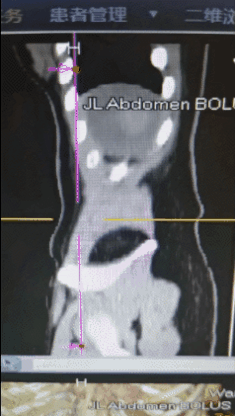

◈ 2022年7月15日,行腹部CT检查提示:盆腔见较大不规则形混杂密度影,与双侧附件及邻近肠管、右侧髂血管分界不清,最大层面约12.4cm×8.8cm,病变上下径约14.9cm,三期CT值约为28Hu、27Hu、31Hu,其内密度不均,可见片状高密度影及钙化密度影,病变周围似见稍高密度包膜影。左上腹部小肠旁另见一相同性质肿块,约4.9cm×3.2cm,边缘强化,与局部肠管分界不清。腹腔内见较多液体密度影。网膜略增厚。

◈ 检查诊断:1、盆腔占位病变,对比2022-04-30片体积稍减小、强化减低。2、腹腔积液,对比前片积液量明显增加;网膜略增厚,请结合临床。3、左上腹部小肠占位性病变,请注意复查。

◈ 考虑肿瘤进展(PD),并且左上腹部小肠占位,考虑转移,腹水量增大。

2022年7月15日 腹部CT